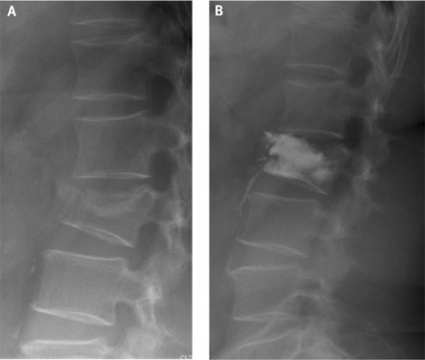

Kotfraktur är en av de vanligaste osteoporosfrakturerna. I de flesta fall är det föregående olycksfallet tämligen trivialt, och kotfrakturen kan vara osteoporosens första kliniska manifestation. Om patienten har neurologiska symtom är kirurgisk behandling indicerad hos osteoporotiker. En kraftig kyfotisk felställning är en annan indikation för kirurgi. Stabilisering på konventionellt sätt och korrektiva operationer av sena deformiteter är emellertid tekniskt svåra och kräver att patienten har ett relativt gott allmäntillstånd. Vertebroplastik och kyfoplastik är två relativt nya behandlingsmetoder vid osteoporotiska kotkompressioner. Genom en perkutant insatt kanyl fyller man den skadade kotkroppen med bencement så att frakturen stabiliseras, ryggsmärtan minskar och det blir lättare att mobilisera patienten. Vid vertebroplastik cementeras ryggkotan i befintligt frakturläge, medan man vid kyfoplastik försöker reducera felställningen med en ballongkateter före cementeringen (Figur 2). Bägge metoderna kan dock ge upphov till komplikationer. Cementläckage in i spinalkanalen och in i segmentella vener samt lungembolier är de mest fruktade. Det finns dock ett explosionsartat intresse för dessa metoder [5], inte minst bland radiologer, och de kommer förmodligen att få ökad användning.